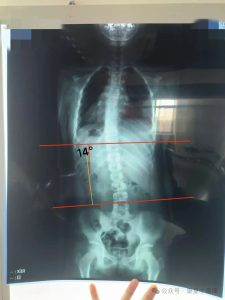

今天给大家介绍一位小朋友,体检后发现脊柱侧弯,于2025年2月16日到店咨询体验。康复前- Cobb角:14°